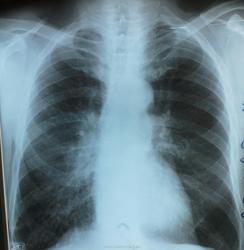

заболевание правого легкого? помогите определиться с заключением

Жалобы на непродуктивный кашель, одышка при нагрузке. Дыхание везикулярное, ослабленное,пневмосклеротические хрипы с обеих сторон, темп. Норма.

в проекции н/долевого бронха тень доп. Образования, сгущение лег. Рисунка нижней доли. Cr?..лаборант зачем-то снял левый бок...ему видимо все равно, какой было снимать.( карте терапевт назначил в 2-х проекциях)

Правый корень, действительно, несколько расширен, внешние контуры - неровные, нечеткие, сгущение легочного рисунка внижне-медиальном отделе правого легочного поля. С-r, конечно, написать можно, но это надо доказывать.

Правый корень совсем плох, дообследовать нужно однозначно

Данных за образование нет.

Обычная эмфизема легких.

По-моему доп. образование в проекции корня, ближе к центральному раку, +гипо средней доли. И лево-право при боковом не сильно влияет. Сначала бы просто пневмонию написать, с контролем для искл. объемного образования. Неделя для онко - не экстренно, (а м.б. боже поможе - и пневмония)

Вот и мой взгляд притянулся туда. Только средне-долевой или нижнедолевой?Но тень доп. Образования явно просматривается.Спасибо.

Судя по прямому снимку, нижнедолевой задействован